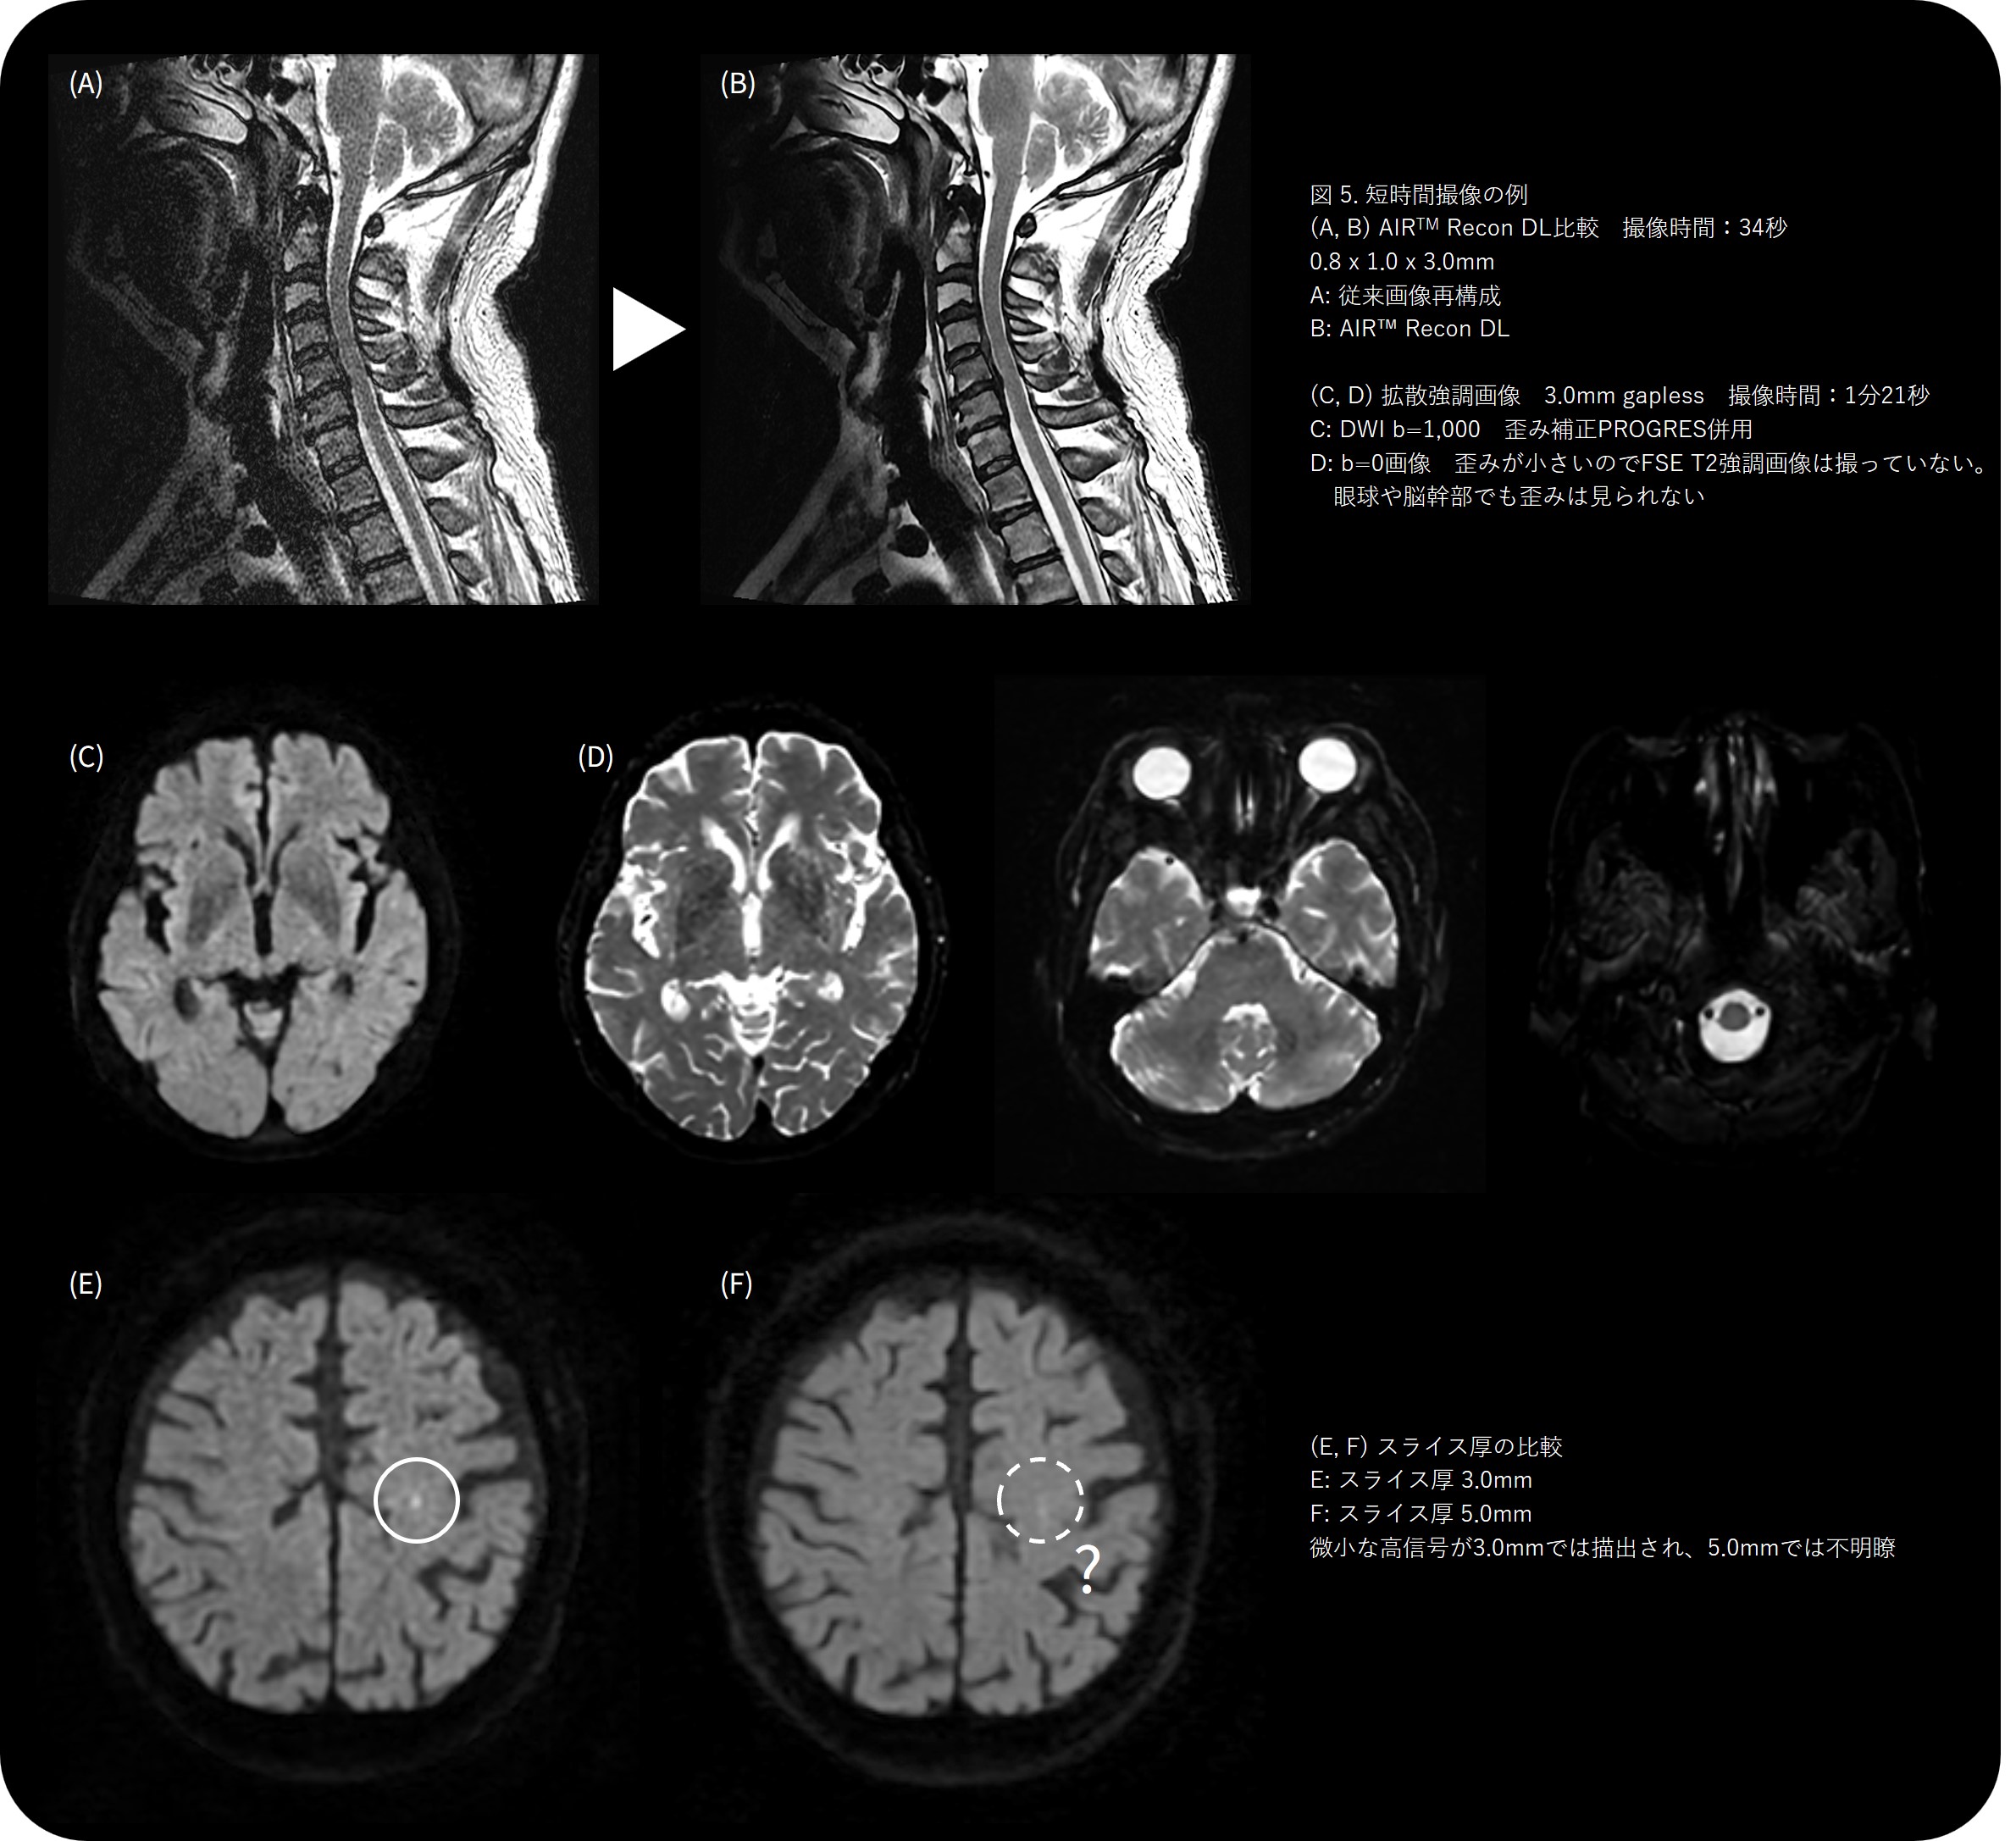

使い勝手の面でも、設定項目が「Low」「Medium」「High」の3段階のみで、他社DLRのような複雑なパラメータ操作が不要です。どの技師が撮像しても安定した品質が得られるため、施設間の画質差も少なく、地方中規模病院でも “均一なクオリティ” を提供できる安心感があります。

さらに、T2 FLEXやT1強調画像をAIR™ Recon DLで撮像し、指関節などの微細構造を1分半程度で描出できるようになりました。以前は10分以上かかっていた検査が短縮され患者負担の軽減とスループット向上の両立を実現しています。